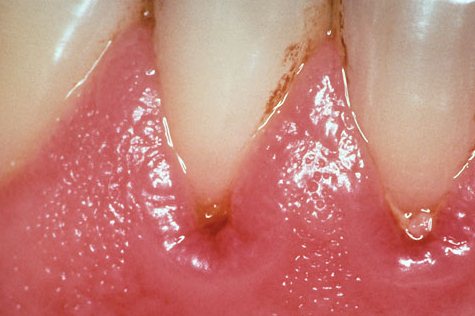

Проявления гингивита зависят от формы заболевания. В наши дни наиболее распространен катаральный гингивит, который имеет следующие симптомы:

Данная форма заболевания характеризуется наличием периодов обострения и ремиссии. Общее состояние больных меняется незначительно, однако, во время обострения катаральный гингивит может вызывать чувство недомогания и субфебрильную температуру. Отметим также, что острый катаральный гингивит, симптомы которого проявляются в периоды прорезывания и смены зубов, отличается ярко выраженными признаками болезни, но хорошо поддается лечению. Хроническая форма более опасна, поскольку симптомы воспаления практически отсутствуют, а значит – лечение начинается уже тогда, когда бактерии приводят к развитию пародонтита и прочих заболеваний ротовой полости.

Гипертрофический гингивит – хронический воспалительный процесс, который отхватывает фронтальные участки обеих челюстей и близлежащие мягкие ткани. В некоторых случаях гипертрофический гингивит у детей является единственным ранним симптомом нарушений эндокринной системы и заболеваний крови, поэтому к его проявлениям стоит отнестись со всей возможной серьезностью. Характерные признаки данной формы – это:

При легких формах гингивита симптомы выражены слабо. Пациенты практически не предъявляют жалоб или жалуются лишь не необычное увеличение десны. Для средней и тяжелой форм характерны ярко выраженные признаки воспаления, сопровождающиеся сильными болями.

Язвенный гингивит (язвенно-некротический гингивит) – является следствием недолеченной катаральной формы. Для начальных этапов заболевания характерны: зуд, отек десен, легкая кровоточивость. Затем язвенный гингивит приводит к появлению некрозов и изъязвлений, покрытых серым или грязно-зеленым налетом. Пациенты чувствуют сильную боль при приеме пищи, гнилостный запах изо рта, жалуются на повышенное отделение вязкой слюны и нарушения сна.